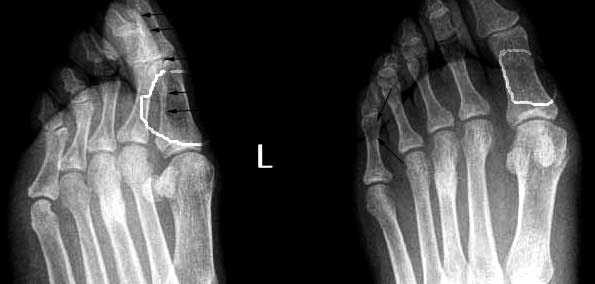

以下是引用常山真人在2004-7-20 9:50:49的发言:[br]第3遮骨疲劳性骨折[br]左足第1趾-似---囊性病变(片不太清晰) 1-正常 2-如是囊性病变多为内生性软骨瘤。[br][br][本贴已被 常山真人 于 2004-7-20 9:53:09 修改过]

以下是引用rjbjl在2004-7-20 21:39:14的发言:[br]应该是第三蹠骨疲劳型骨折[br]zhi骨

以下是引用www123456在2004-7-20 23:17:45的发言:[br]典型的第三跖骨 疲劳骨折。[br]对于第一趾骨的病变怀疑是没有根据的,斜位所见影像是由于第一趾的跖趾关节软组织和骨皮质凑成的。在正位片可见第一趾的骨质是完好的。